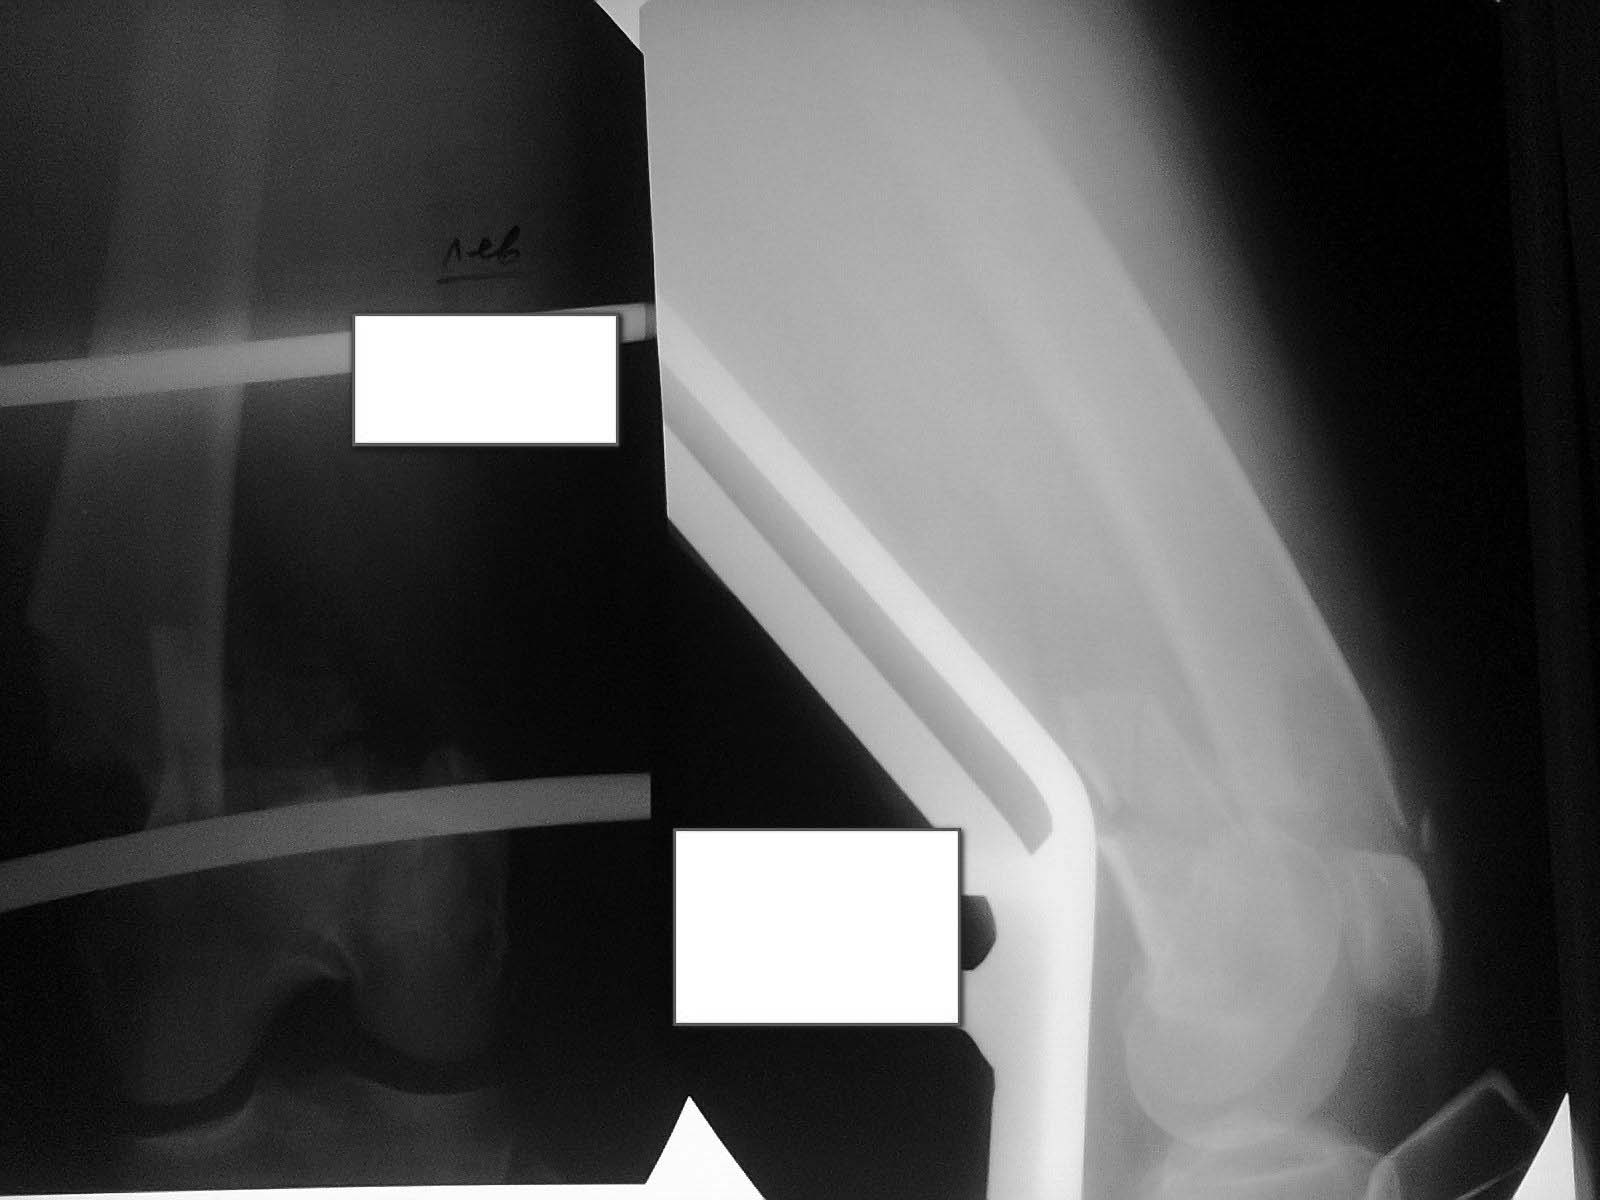

Представляю пациентку Д., 57 лет.Пострадала в ДТП в августе 2014

г.Диагноз:Открытый оскольчатый внутрисуставной перелом дистального

метаэпифиза левой бедренной кости со смещением отломков. Рваные раны и

ссадины левых бедра и голени. Закрытый перелом V ребра слева без

смещения отломков. Травматический шок I ст(снимок 1).